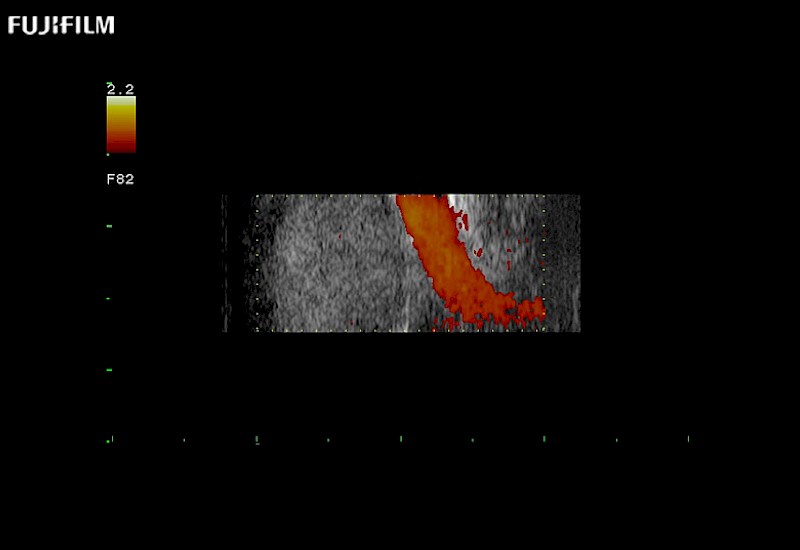

Extraordinary high-resolution digital imaging

Multi-Parametric imaging modalities